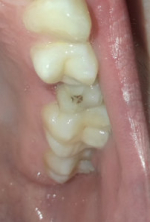

Осталась одна стенка зуба

После повреждения осталась лишь одна стенка? Такая ситуация не особо критична, ровно как и если у вас откололась небольшая часть зуба (рекомендуем прочитать: что делать, если кусочек зуба откололся?). В таких случаях восстановить здоровье десны и зубов можно с помощью:

- использования коронки,

- полного наращивания с использованием штифтов.

В варианте с наращиванием вам придется платить за штифты и материал, соответственно цена будет зависеть от материала. Чем хорош такой способ? После наращивания зуб будет выглядеть как родной и иметь идеальную форму, нервные каналы и корень зуба будут защищены от воздействия внешних факторов. При использовании высококачественных материалов данная конструкция никогда не отломится.